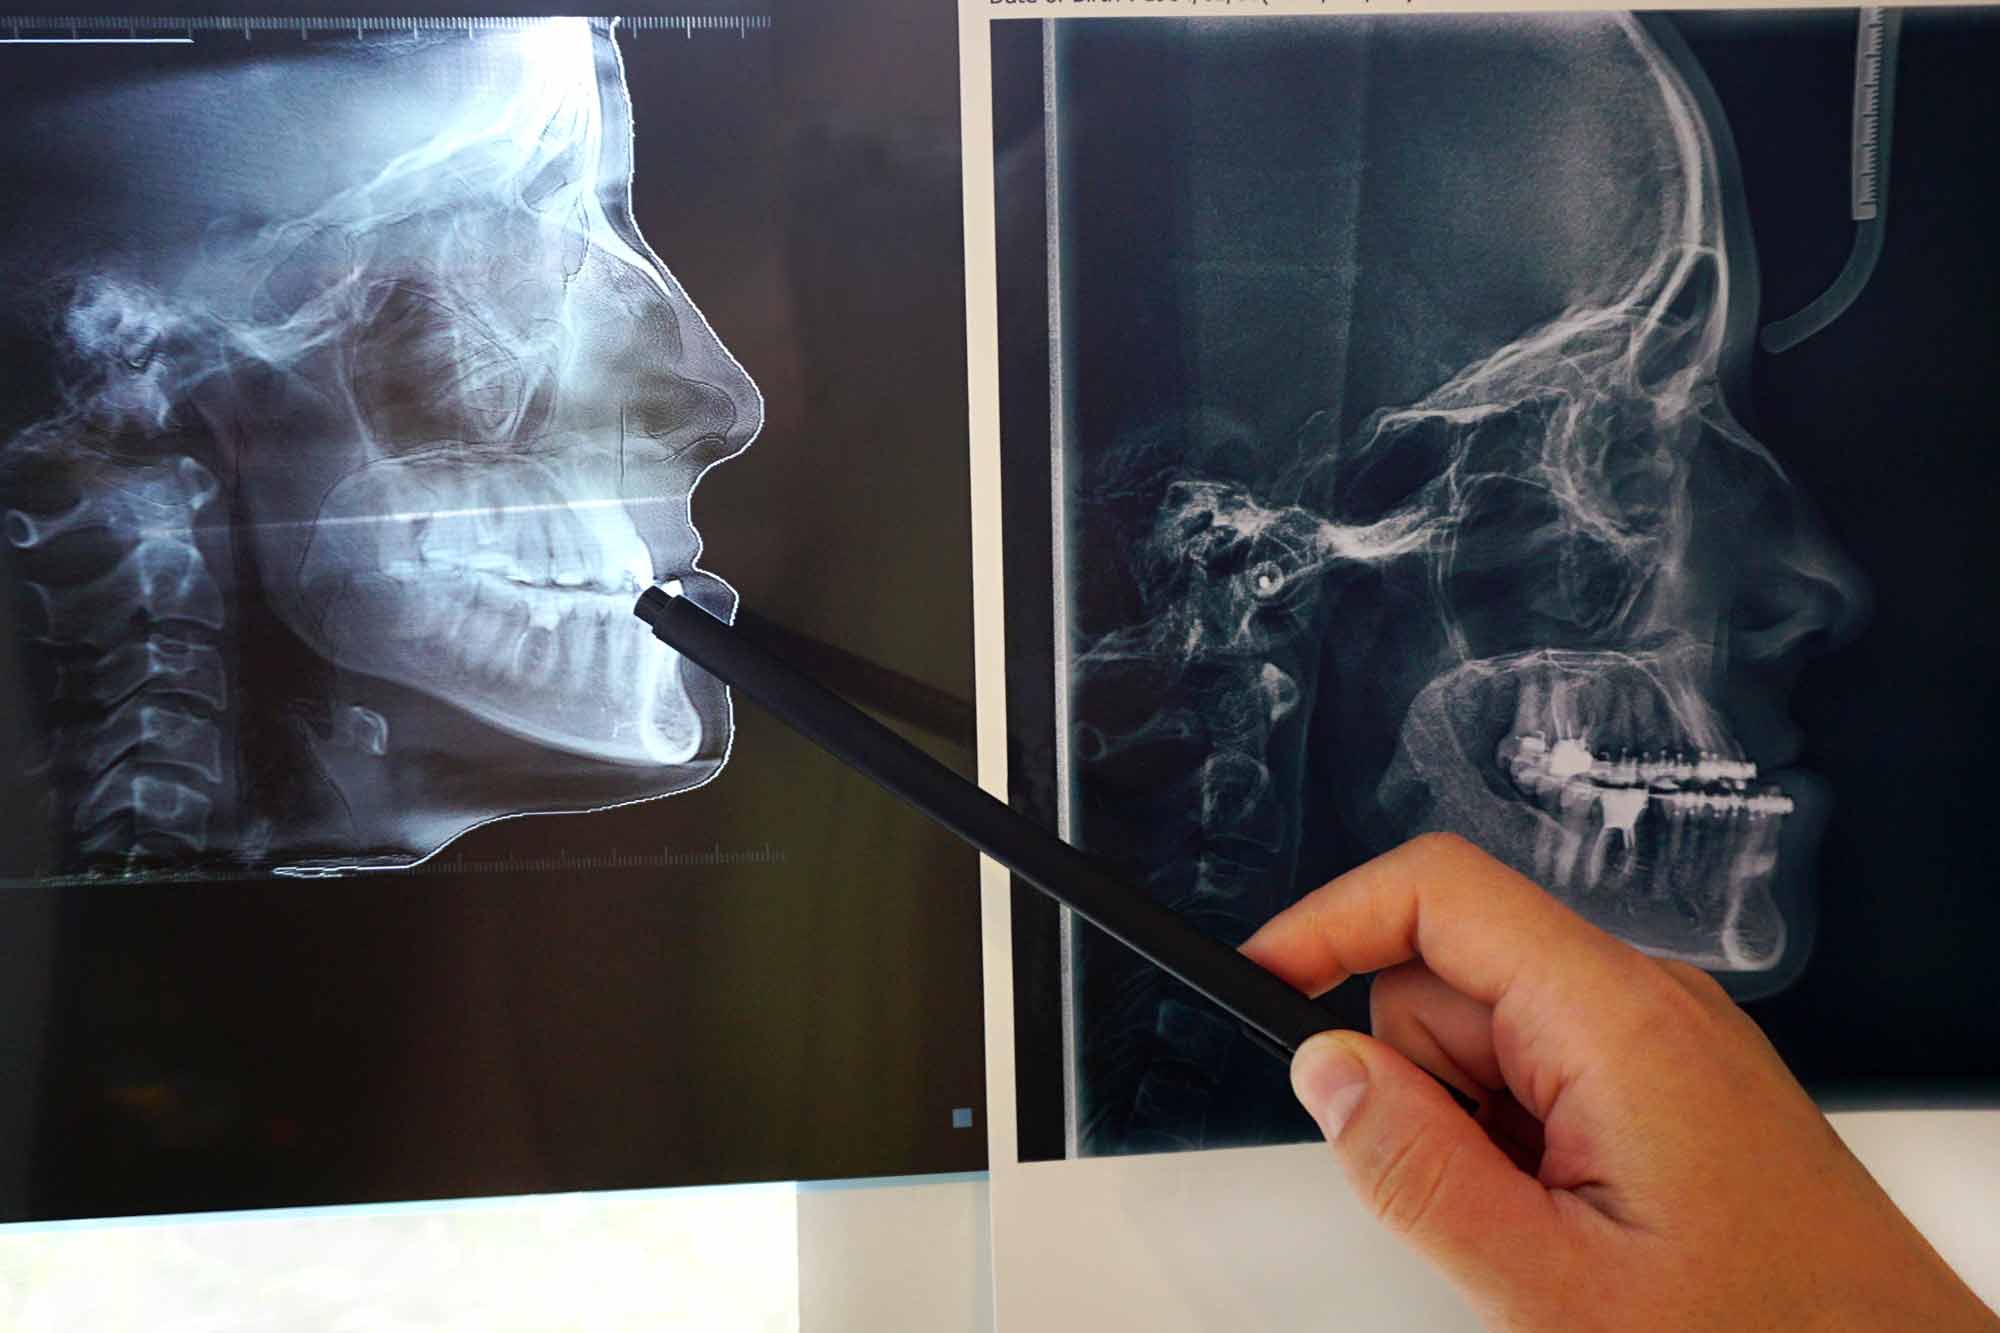

Accidents happen. When they do, you can be left with trauma to the face or jaw. Our team of oral and maxillofacial surgeons can skillfully evaluate your case and offer expert opinions on corrective facial trauma treatments based on our years of training. From orbital fractures and cracked teeth to facial lacerations and jawbone problems, we can help you recover after suffering an unexpected injury.

It can be a great relief to work with an oral surgeon after you’ve experienced a facial trauma. Frequently, facial trauma affects more than just the immediate area. A well-trained oral surgeon can help you address or avoid correlating oral problems that a different doctor may overlook.